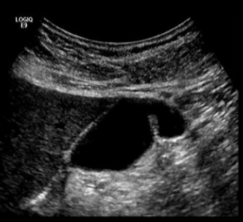

Cholelithiasis